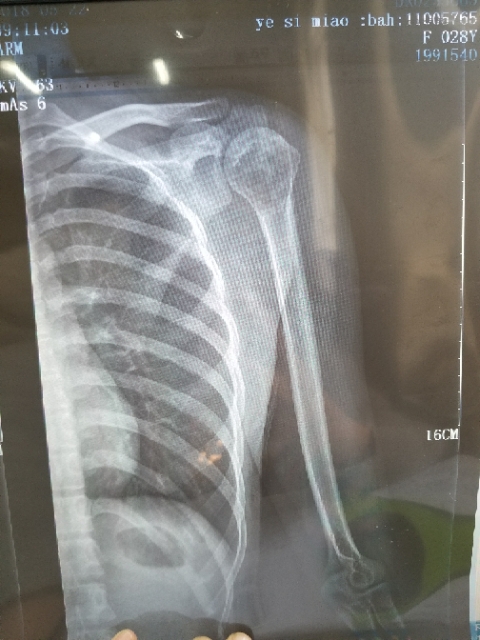

身心俱疲斗争 02019-02-22 患者家属女儿14岁,明天做截肢手术。医生让从髋关节处截,想保留个七八公分。问问大神们髋关节以下留七八公分能用常规的假肢吗? ...

X-man 02019-01-22 患者本人十九岁,九月十号因恶性骨肉瘤在云南省肿瘤医院做了截肢手术,后发现肺上有三个结节,一个大约一厘米,两个不足一厘米,请问...